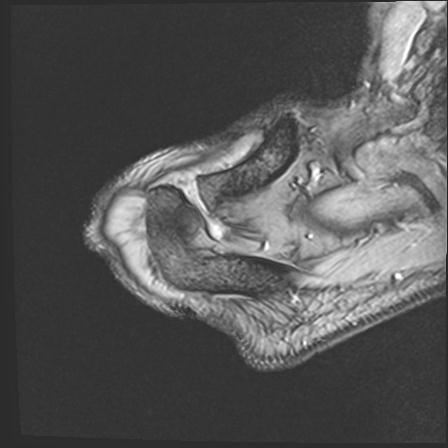

56476 8/28 4R 1/21 2R 左足関節 デジカメ写真 72歳女性 右足関節AS